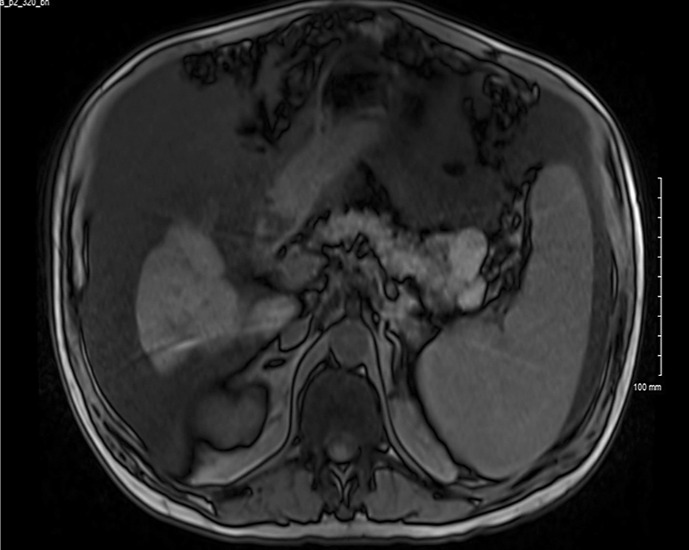

Case presentation: We report a rare case of a 63-year-old male cirrhotic patient who presented with a pancreatic body/tail mass, which was later confirmed to be an MANEC. He was initiated on neoadjuvant chemotherapy with FOLFIRINOX, but unfortunately died before surgery.